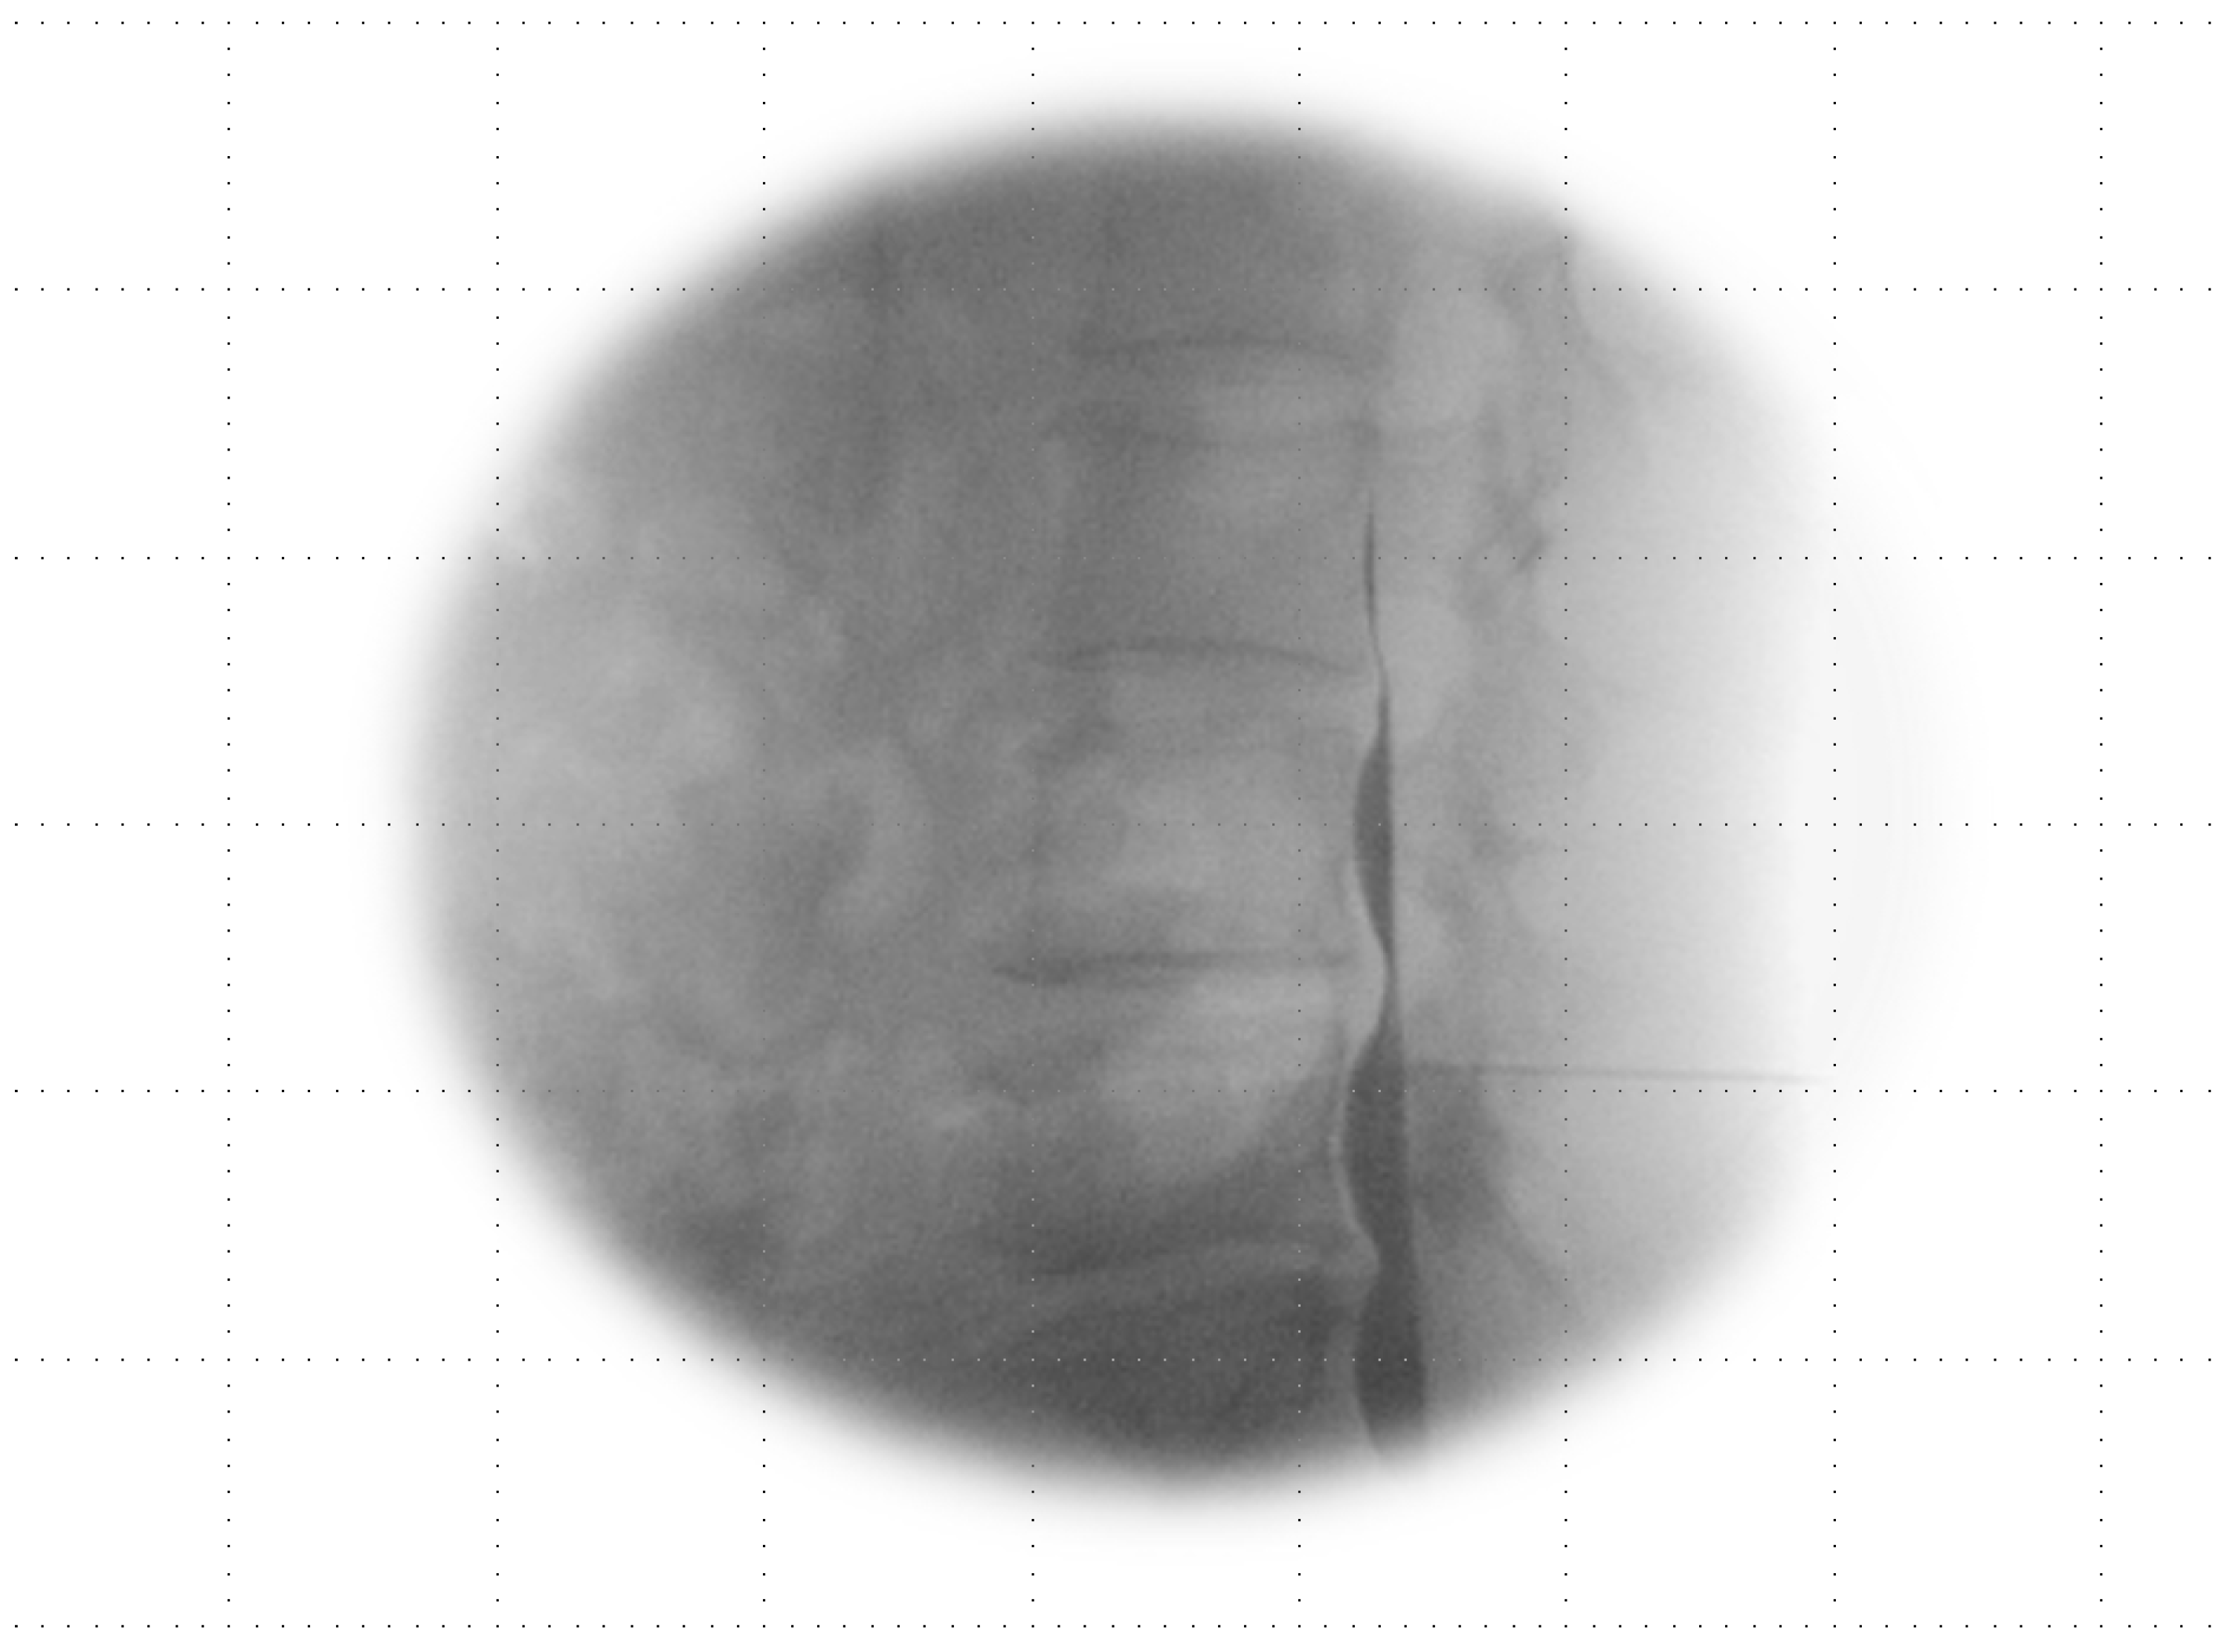

If the Tuohy needle was positioned within the subarachnoid space (Figure 3) or straddled both the subdural and subarachnoid spaces (Figure 4A–C), it was removed, and epidural anesthesia was attempted at a different level.

Figure 3.

Subarachnoid image in lateral view: a single-layer image shows a pattern of hyperbaric contrast medium in the most ventrally dependent region featuring ventral undulations attributable to the arachnoid mater when in the prone position. There is a line of lucency between the contrast spread and the posterior vertebral body, suggestive of the area pertaining to the anterior epidural–subdural space.